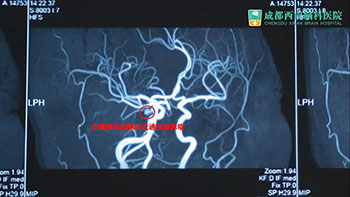

晏女士在医生的建议下,转入我院寻求黄光富教授的治疗。经检查,发现她左侧眼睑下垂,不能自己睁开。扒开眼皮,左瞳孔放大,对光反射消失,眼球偏外,且不能正常转动。头颅MRA检查后,确诊为左侧颈内动脉后交通段动脉瘤,拟行动脉瘤夹闭手术。

术前影像学检查

颅内的脑动脉瘤是引起动眼神经麻痹的重要原因,占原因的20--30%,虽然比例不是较高,却较凶险。因为脑动脉血管壁薄弱,受血流冲击,血管壁就像吹气球一样鼓了一个血管瘤,压迫临近的动眼神经,从而造成动眼神经麻痹症。其中,后交通动脉瘤随时可能在压力很高的动脉血流冲击下,引起瘤壁破裂,造成致命性大出血,被形象地称为脑内的“不定时炸弹”。